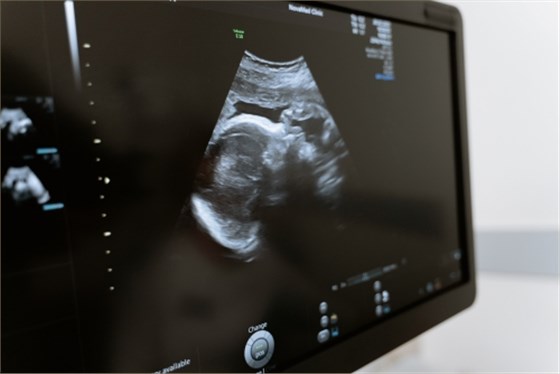

上肢血管超聲檢查是通過超聲檢查血管壁、血管內(nèi)血流情況的技術(shù)。一般情況下,上肢血管超聲檢查可用于診斷動脈硬化、靜脈狹窄、動靜脈瘺、血栓閉塞性脈管炎、靜脈血栓形成等疾病。